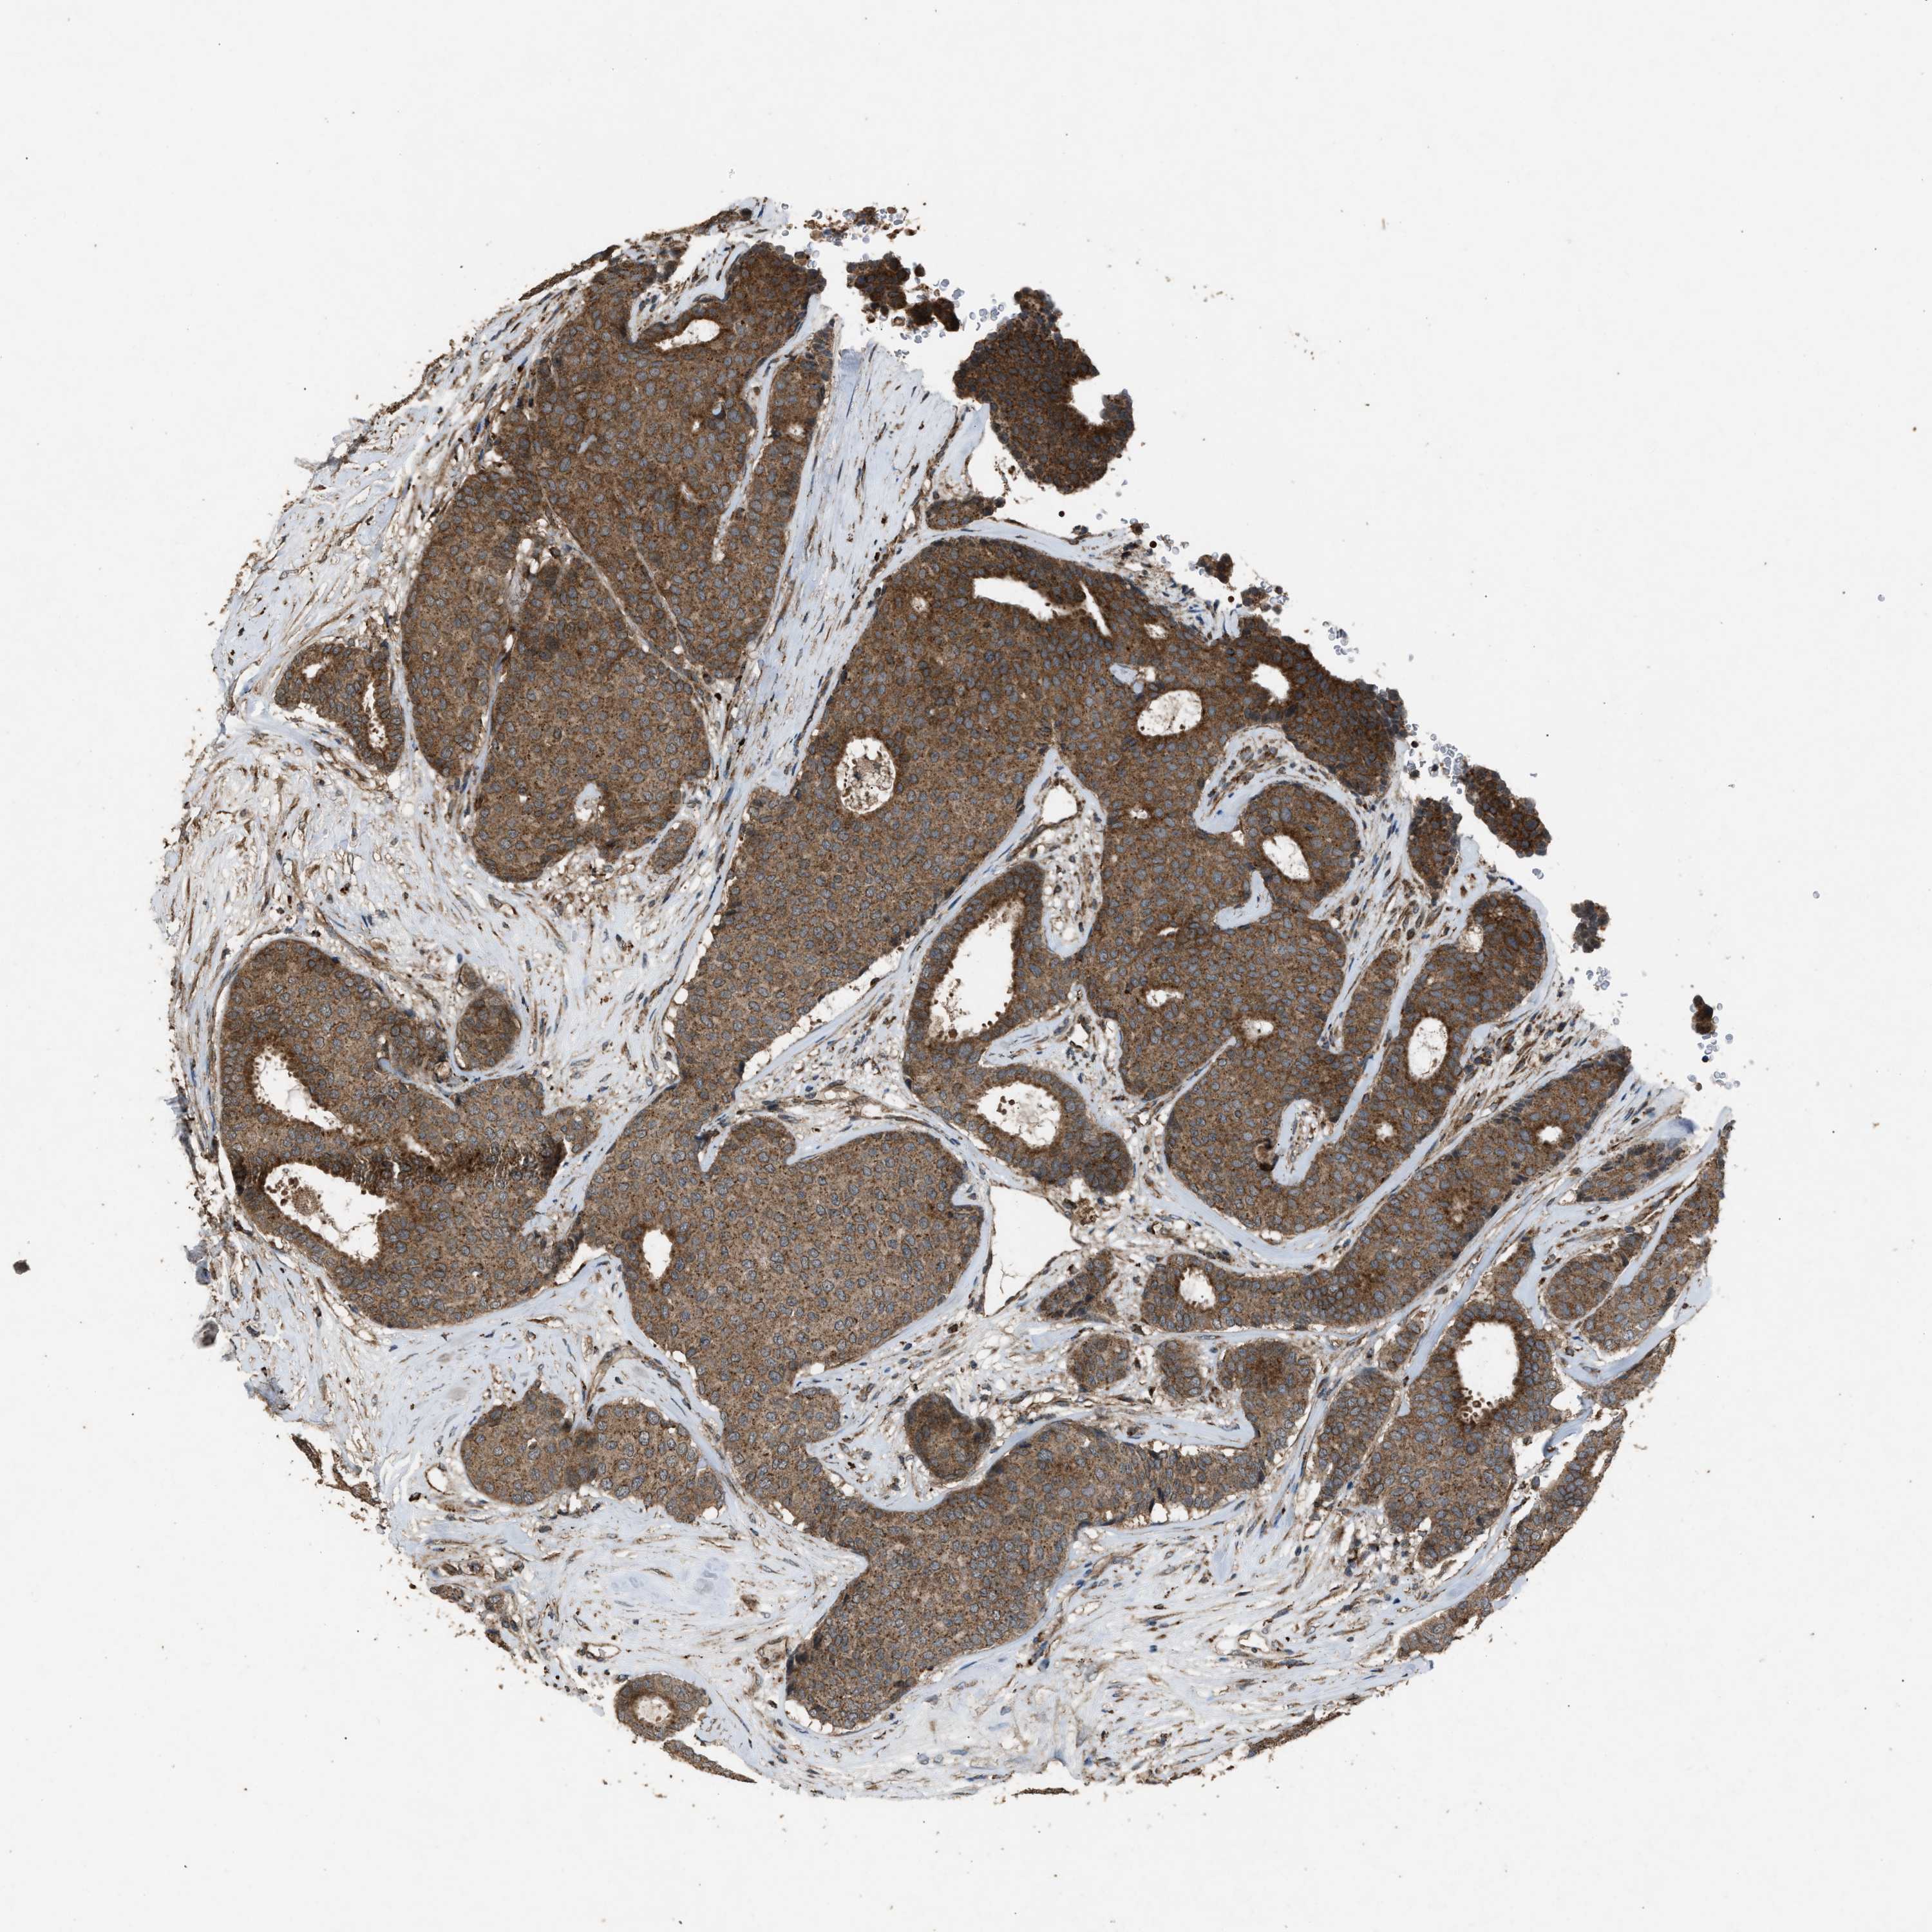

CANCER BREAST CANCER Show tissue menu

BRCA TCGA BRCA VALIDATION PROTEIN EXPRESSION